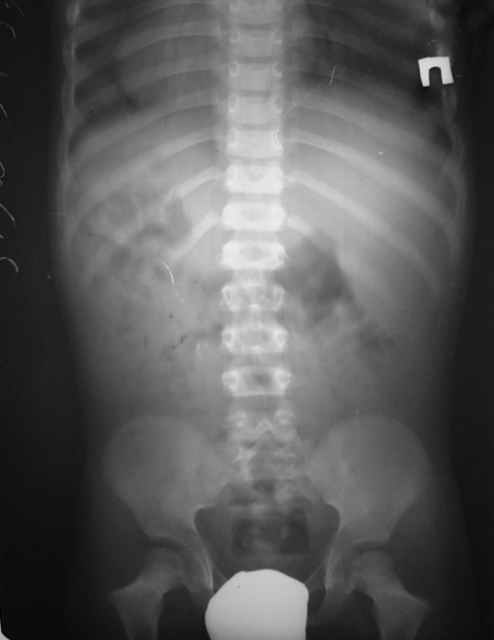

Мальчик, 5 лет. Гипохондроплазия. Генетическая предрасположенность к нарушению физического развития. Ребенок от I беременности, протекавшей нормально. ТОРЧ-негативный. Неврологических расстройств нет. Семейный анамнез: средний рост мужчин в семье 150 см, антропологические особенности - короткие конечности, длинное туловище, крупный череп. Вес 15 кг, рост 92 см.Тактика лечения? Заранее благодарю! С уважением,А.В.Владзимирский